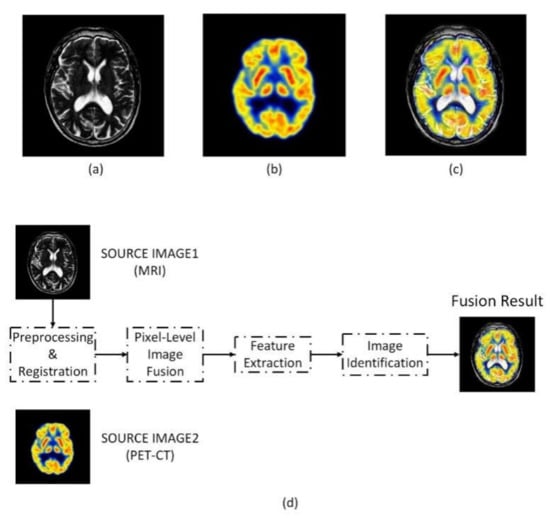

2.4. Multimodal Pixel-Level Image Fusion

3.1. Multimodal Image Fusion Results